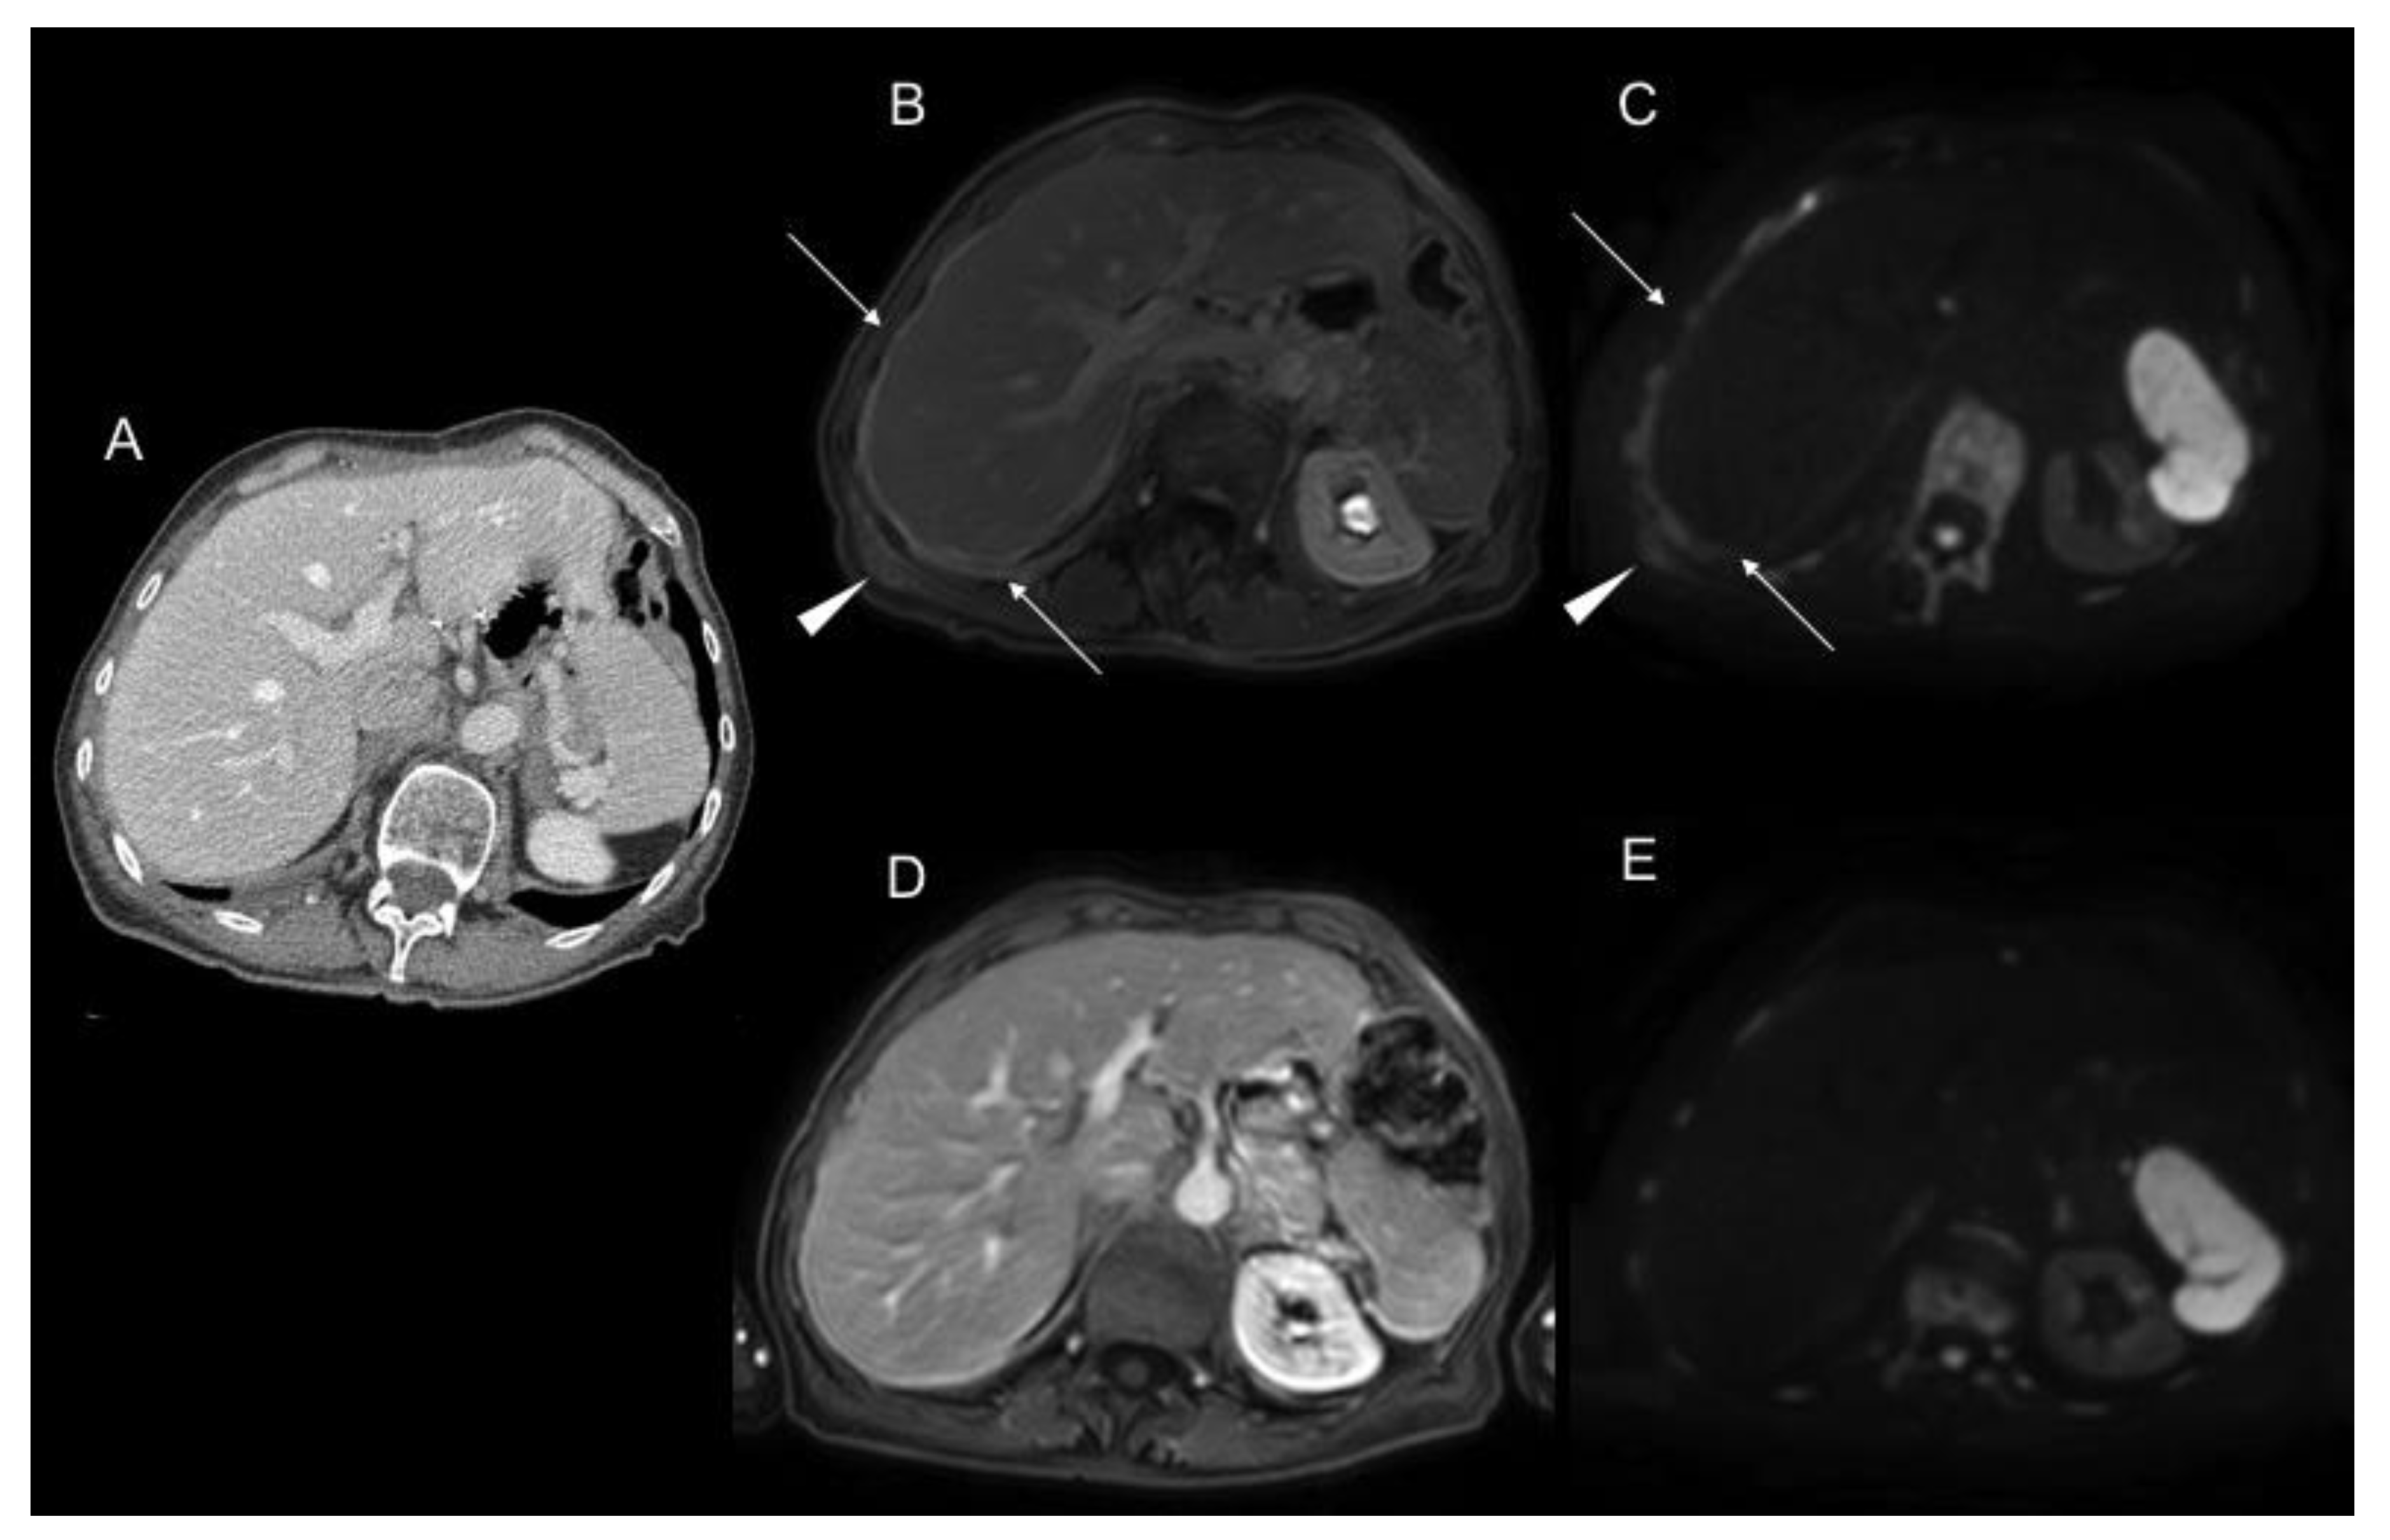

2.2. Magnetic Resonance Imaging (MRI)

- De Vuysere, S.; Vandecaveye, V.; De Bruecker, Y.; Carton, S.; Vermeiren, K.; Tollens, T.; De Keyzer, F.; Dresen, R.C. Accuracy of whole-body diffusion-weighted MRI (WB-DWI/MRI) in diagnosis, staging and follow-up of gastric cancer, in comparison to CT: A pilot study. BMC Med. Imaging 2021, 21, 1–9. [Google Scholar] [CrossRef] [PubMed]